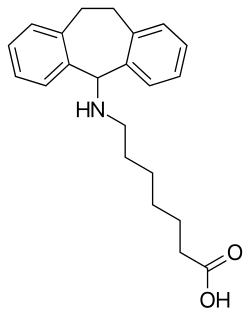

Non-selective norepinephrine reuptake inhibitors

- Amitriptyline

- Amoxapine

- Clomipramine

- Cocaine

- Desipramine

- Imipramine

- Indeloxazine

- Maprotiline

- Mazindol

- Mianserin

- Nortriptyline

- Protriptyline

- Setiptiline

- Tapentadol

- Teniloxazine

- Tramadol